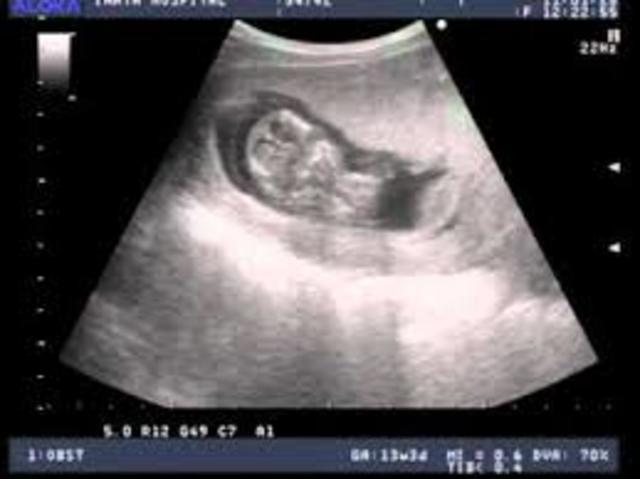

~ First ultrasound scan

~ Mom can learn the sex of the baby.

~ First look at the baby

~ She can feel the baby move during the ultrasound

~ More detailed ultrasound to tell if there is any abnormalities